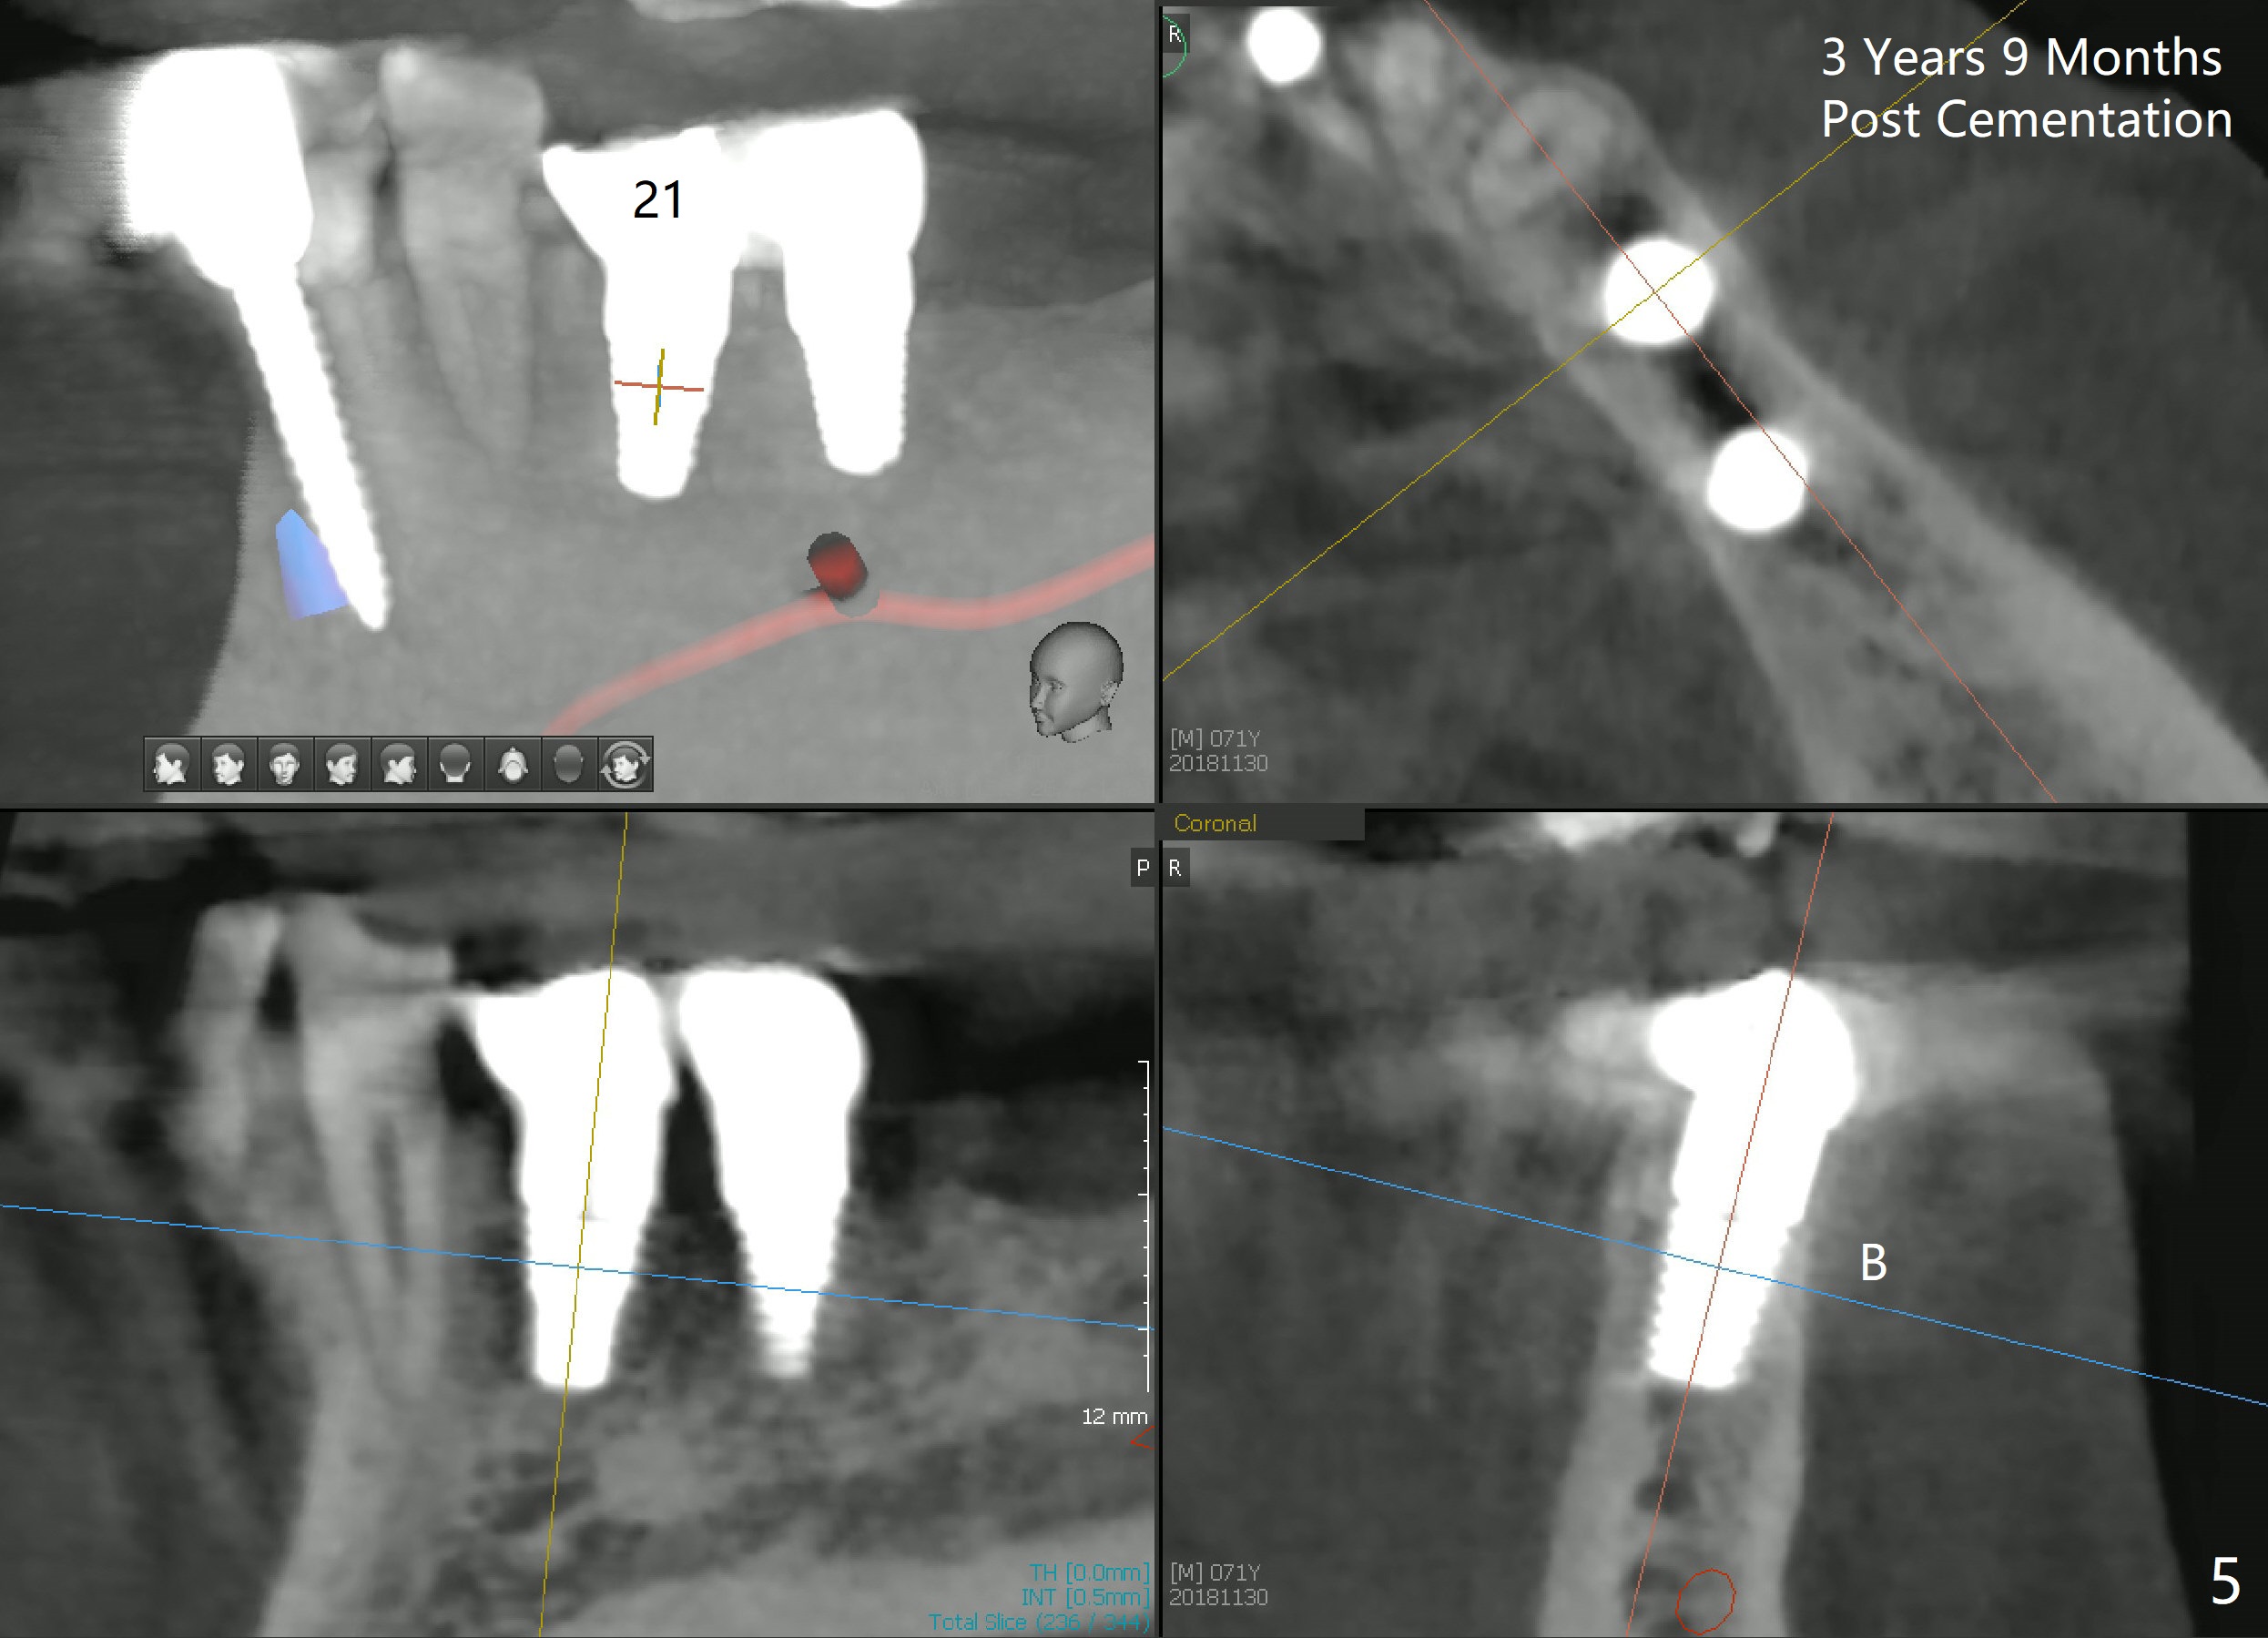

Two implants are to be placed at the sites of #20 and 21 (Fig.1 CT sagittal section) to be used as ortho anchorages. When paralleling pins (Fig.2 P) are inserted, they happen to be in the original sockets (arrowheads). Two 4.5x11 mm implants are also placed more or less in the original sockets (Fig.3). Postop X-ray is shown. Two separate provisional crowns are to be fabricated with the occlusal table of #20 being lower, since #13 has mobility and has supraerupted. Leave a space (1-2 mm) mesial to #21 provisional so that the tooth #22 and 23 can be moved distally. A premolar band is going to be placed at #21. There is no bone loss 2.5 years (Fig.4) or 3 years 9 months (Fig.5,6 CT) post cementation. Return to Implant & Ortho Full Mouth Reconstruction 3 24/26 28 30 Xin Wei, DDS, PhD, MS 1st edition 10/04/2014, last revision 12/16/2018